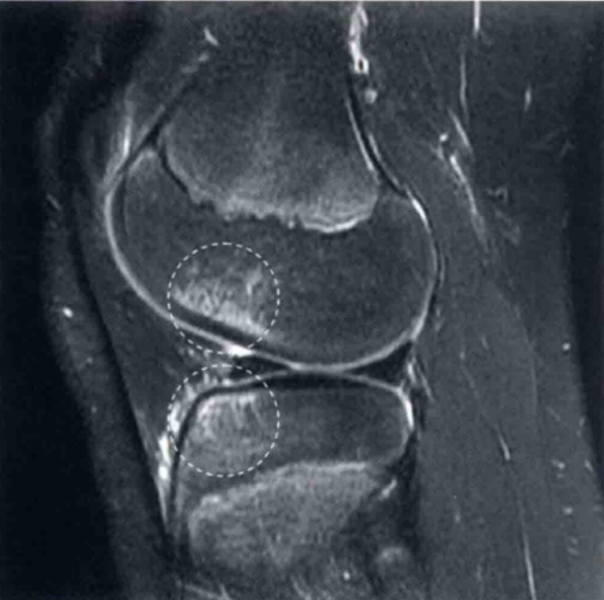

图8 a和b显示在T2和质子加权像上为正常的PCL,可见正常的弧度和在两个序列中为均值低信号

图9 a和b显示的为矢状位质子加权像和T2上PCL损伤的图像(箭头)。PCL变厚、水肿,但不是完全的断裂